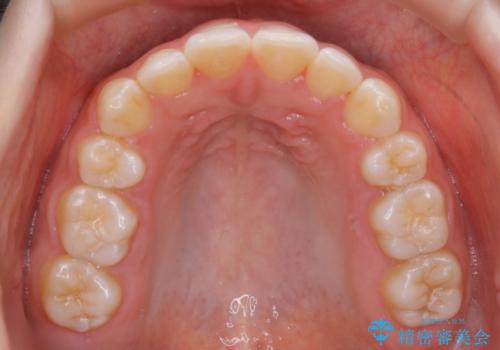

【非抜歯】上下の前歯が噛み合わないオープンバイトの治療

- 噛み合わせの不調を主訴にご来院されました。

骨格的な問題もあり、噛んだ時に奥歯しか当たらず前歯の被蓋があまりない状態でした。

奥歯を沈めて噛み込みを深くしていくことで被害の改善が起こるとともに、下顎自体が前上方に回転移動することで顔貌的にも変化を出すことができます。

臼歯の位置が高く噛んだ時に奥歯しか当たらなかったり、舌癖などが原因で前歯が前に倒れてしまうことで上下の前歯の被蓋がなくなってしまっている状態をオープンバイトといいます。

前者の場合は臼歯を圧下し沈めてあげることで改善させます。後者の場合は前方に傾斜している歯を元の角度に戻してあげることで改善しますが、舌癖がある場合はその癖自体を無くす治療をしない限りまた同じ状態へと後戻りしてしまいます。